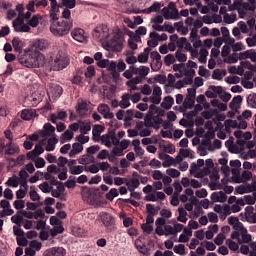

Setup. We evaluate all models on the Camelyon16 Whole Slide Image cancer detection dataset (Bejnordi et al., 2017). Each instance consists of a high resolution image of tissue from a medical scan which is pre-processed into patches of RGB pixels. After pre-processing, the average number of patches in a single set is over 9,300 (7.3GB), making each input roughly equivalent to processing 1% of ImageNet1k (Deng et al., 2009). The largest input in the training set contains 32,382 patches (25.4 GB). We utilize a ResNet18 (He et al., 2016) which is pretrained on Camelyon16 (Li et al., 2021) via SimCLR (Chen et al., 2020) as a backbone feature extractor whose weights can be downloaded from this repository111https://github.com/binli123/dsmil-wsi. Our goal is to first pretrain MBC set encoders on the extracted features, and then use the unbiased estimation of the full set gradient to fine-tune the feature extractor on the full input sets. We evaluate the performance of UMBC against non-MBC MIL baselines: DS-MIL (Li et al., 2021) and AB-MIL (Ilse et al., 2018), as well as MBC baselines: DeepSets and SSE.

The Camelyon16 Whole Slide Image dataset consists of 270 training instances and 129 validation instances. The dataset was created for a competition, and therefore the test set is hidden. We therefore follow the example set by previous works (Li et al., 2021) and report performance achieved on the validation set. For preprocessing, we consider the slide magnification setting, and use OTSU’s thresholding method to detect regions containing tissue within the WSI. We then split the activated regions into non overlapping patches of size . An example of single input patches can be seen in Figure 12. The largest input set contains image patches which are each . All patch extraction code can be found in the supplementary file. Table 14 contains statistics related to the numbers of patches per input for the training and the test set as well as the distribution of positive and negative labels.